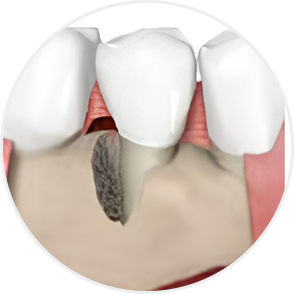

심한 치주질환으로 잇몸이 내려앉고 치조골이 흡수된 경우에도

엠도게인을 이용한 ‘잇몸재생술’을 통해

치아를 보존할 수 있습니다.

이 술식은 손상된 잇몸뼈와 주변 조직을 재생시키는 치료로,

엠도게인이라고 하는 잇몸조직을 재생시키는

주사를 사용하여 치아의 지지 구조를 다시 세워줍니다.

그 결과 치아를 뽑지 않고 기능과 건강을 회복할 수 있도록 돕습니다.